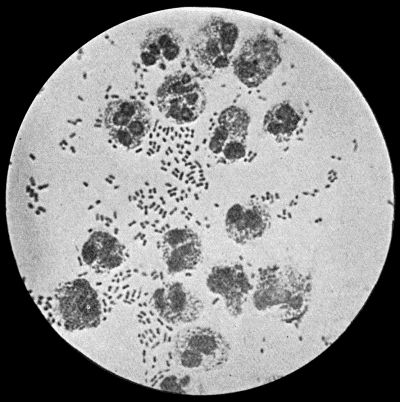

Cocci or micrococci are minute round bodies, averaging about 1 µ in diameter. The great majority are non-motile. They multiply by fission; and when they divide in such a way that the resulting cells remain in pairs, are called diplococci, of which the bacteria of gonorrhœa and pneumonia are examples (Fig. 5). When they divide irregularly, and form grape-like bunches, they are known as staphylococci, and to this variety the commonest pyogenic or pus-forming organisms belong (Fig. 2). When division takes place only in one axis, so that long chains are formed, the term streptococcus is applied (Fig. 3). Streptococci are met with in erysipelas and various other inflammatory and suppurative processes of a spreading character.

Staphylococcus Aureus.—This is the commonest organism found in localised inflammatory and suppurative conditions. It varies greatly in its virulence, and is found in such widely different conditions as skin pustules, boils, carbuncles, and some acute inflammations of bone. As seen by the microscope it occurs in grape-like clusters, fission of the individual cells taking place irregularly (Fig. 2). When grown in artificial media, the colonies assume an orange-yellow colour—hence the name aureus. It is of high vitality and resists more prolonged exposure to high temperatures than most non-sporing bacteria. It is capable of lying latent in the tissues for long periods, for example, in the marrow of long bones, and of again becoming active and causing a fresh outbreak of suppuration. This organism is widely distributed: it is found on the skin, in the mouth, and in other situations in the body, and as it is present in the dust of the air and on all objects upon which dust has settled, it is a continual source of infection unless means are taken to exclude it from wounds.

Fig. 3.—Streptococci in Pus from an acute abscess in subcutaneous tissue. × 1000 diam. Gram's stain.